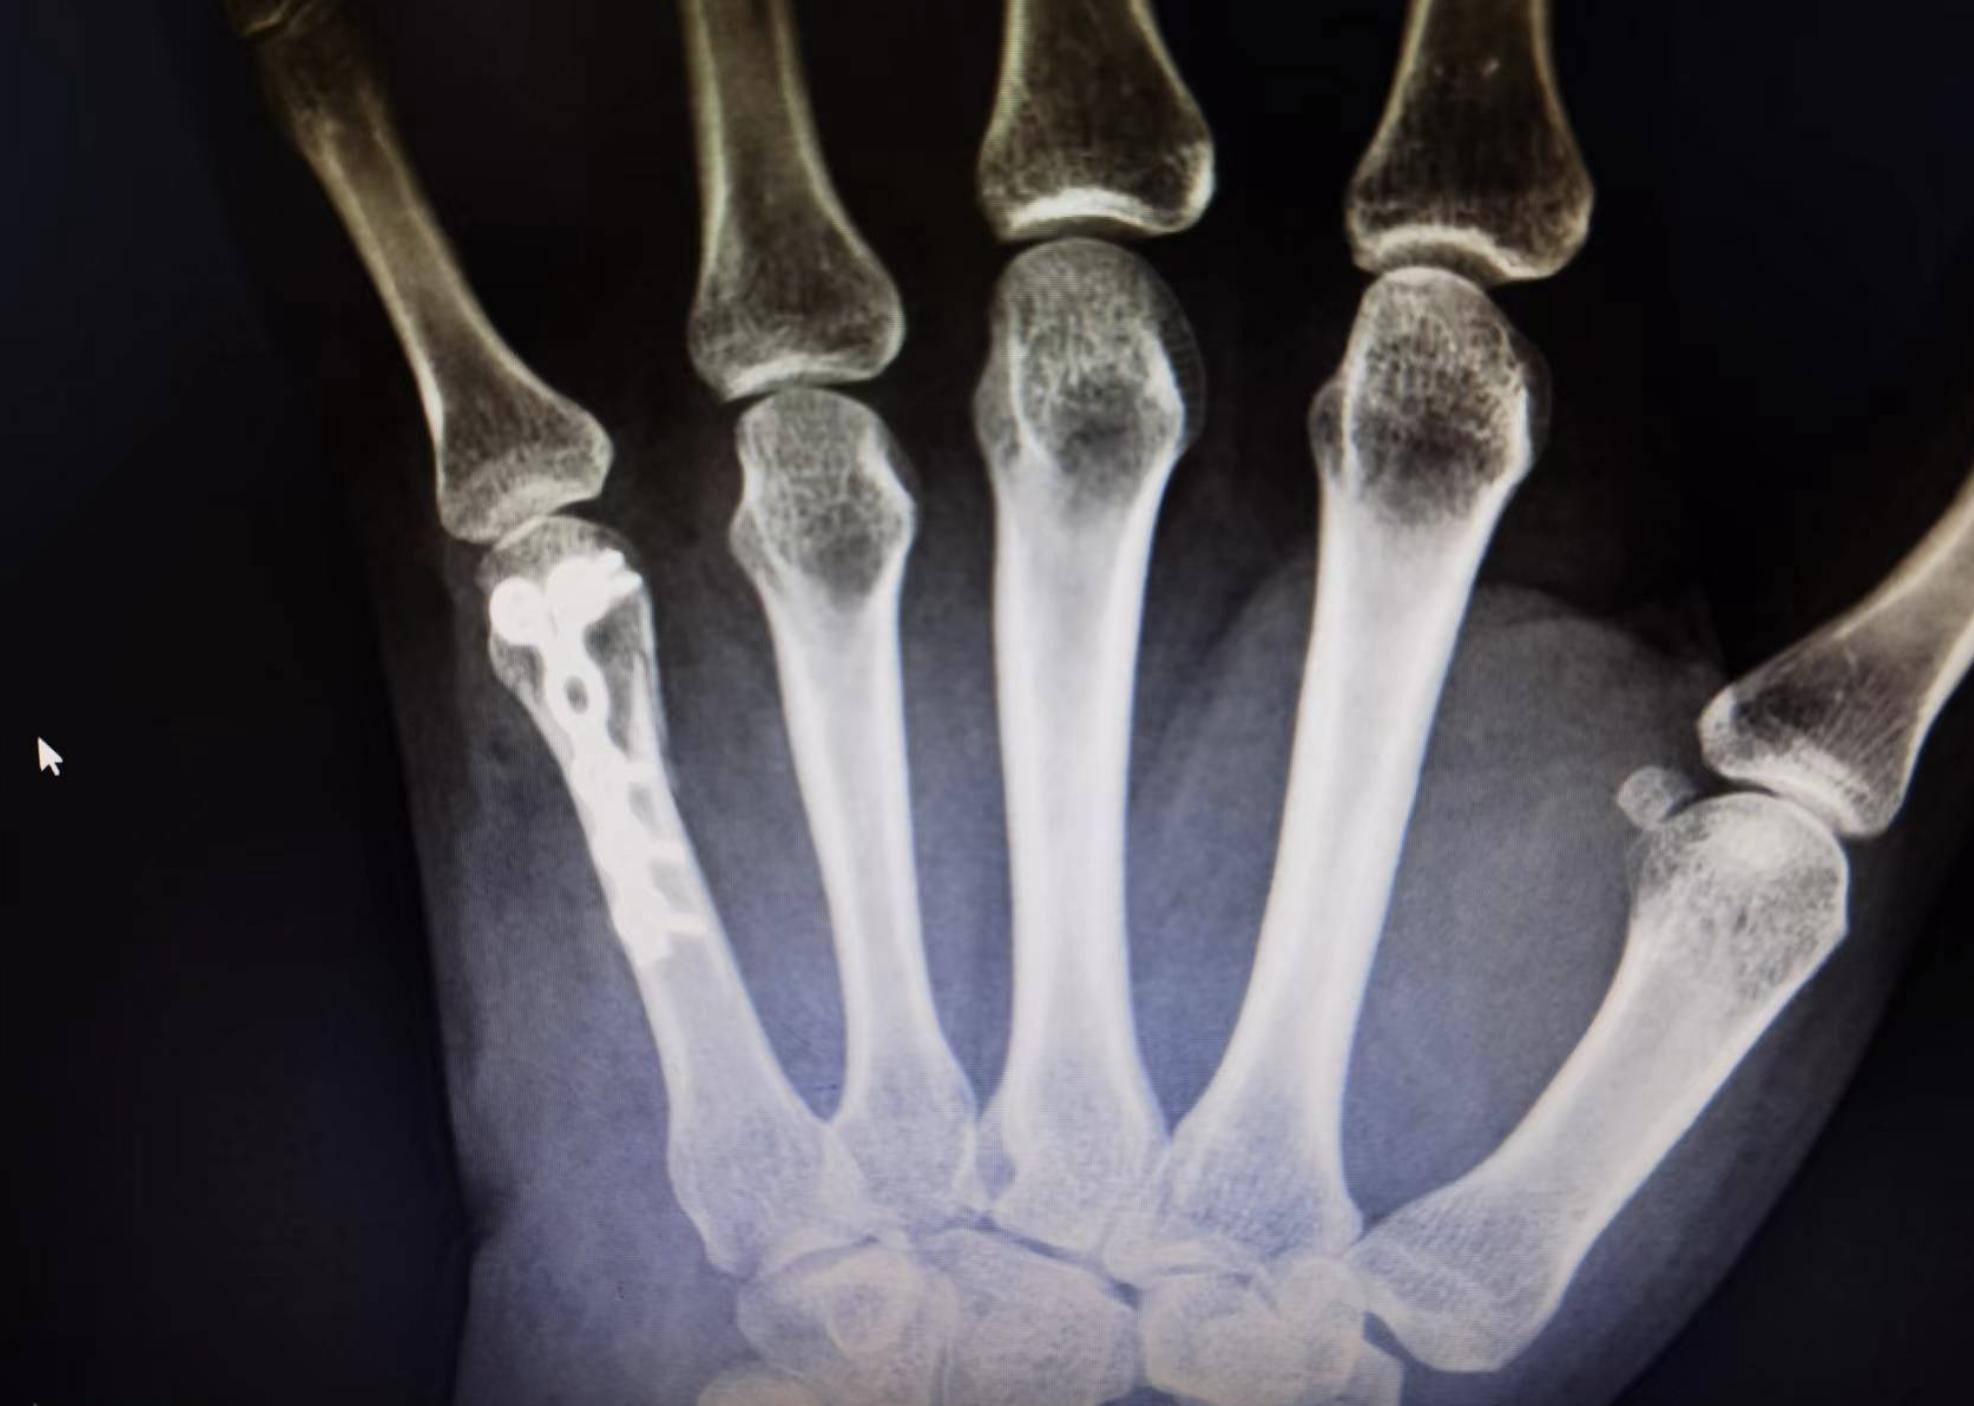

术后影像图

段女士在手术后,自诉情况尚可,疼痛得到明显减轻,肿胀情况也得到明显改善,切口愈合良好,左手手指活动、血运及感觉都很好。术后复查CT,提示:左手第5掌骨骨折端对位对线良好,内固定牢固,病情好转。

之后,为段女士进行左第五掌骨骨折切开复位内固定术,对手术部位进行常规消毒、铺中后,沿在第五掌骨背侧纵行切开皮肤,皮下,显露伸肌腱并牵开保护,见第五掌骨头Y型骨折,明显移位,牵引背伸掌指关节复位克氏针临时固定,透视位置良好,以掌骨锁定钢板+4枚锁定螺钉固定,再次透视见骨折对位对线良好,生理盐水及防粘连冲洗液冲洗后,彻底止血,放置可吸收止血膜,逐层缝合手术切口、千洁敷料包扎,手术过程很顺利,段女士安全回到病房。